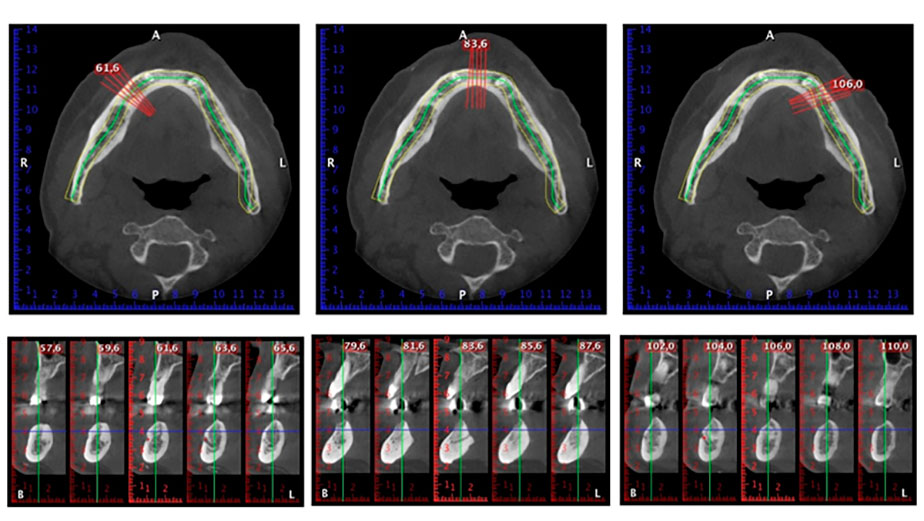

Para la planificación y la minimización del riesgo, se realizó una tomografía volumétrica tridimensional (TVD, Planmeca) que mostró que la calidad y la cantidad del tejido óseo era suficiente para la intervención quirúrgica y el tratamiento inmediato con el método Fast & Fixed. Siguiendo el protocolo de este método, se insertaron los implantes en la región de las piezas 35, 32, 42 y 45. Debido a la inclinación de hasta 45 grados de los implantes distales, el perfil de emergencia se desplazó hacia posterior y se generó un mayor polígono de soporte (fig. 3).

método Fast & Fixed

Fig. 3